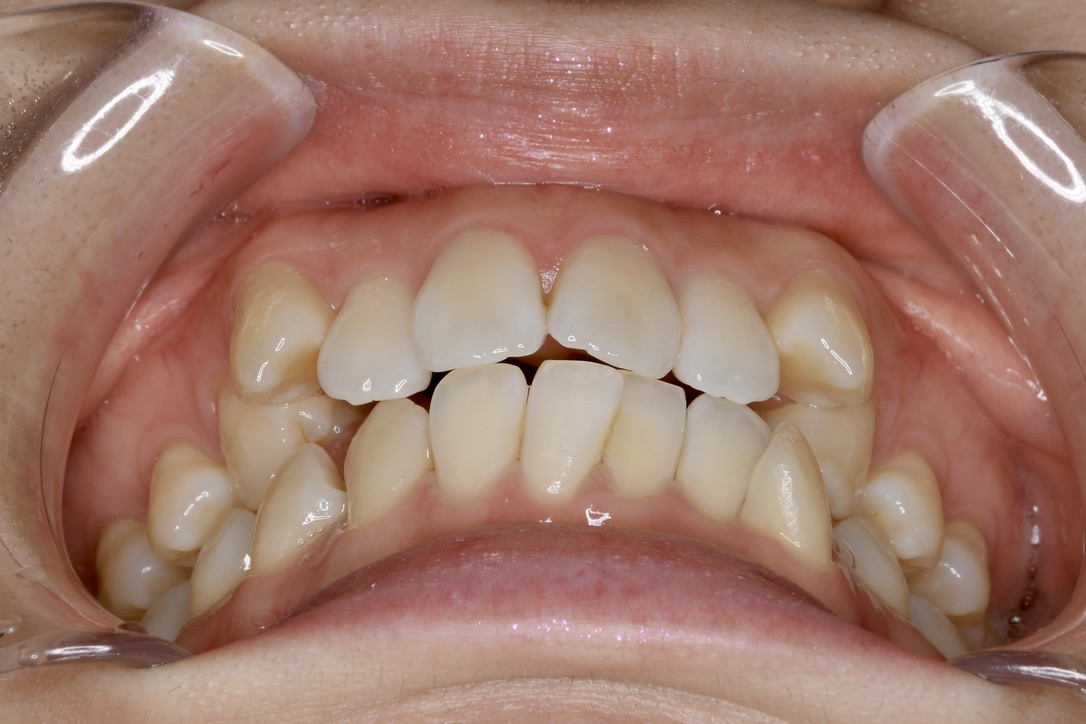

| 主訴 | 写真を見て歯並びが気になる。特に下の前歯はガタガタが強く治したい。 |

|---|---|

| 診断名・主な症状 | 叢生 |

| 年齢 | 19歳 |

| 治療内容 | 上下とも歯並びの幅を広げることでできたスペースを利用して、ガタガタを解消しました。 |

| 使用装置 | 表側矯正(ワイヤー) 矯正用ミニインプラント |

| 抜歯部位 | 抜歯なし |

| 治療期間 | 1年10ヶ月 |

| 通院回数 | 25回 |

| 費用 | 91万円程度(税別) 220 |

| リスク・副作用 | 痛み、歯肉退縮、歯根吸収、抜歯に伴う出血や腫れが生じることがあります。 |